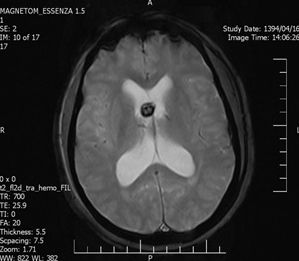

An Occipital Headache as the First Presentation of Multiple Third, Fourth, and Lateral Ventricular Cavernous Malformations: A Case Report and Review of Literature

Background: Cavernous hemangiomas are common benign vascular malformations. Their existence in the intraventricular region is very rare. Case Reports: A 43-year old woman with an occipital headache was admitted to the emergency ward. Brain computed tomography scan showed mild hydrocephalus and multiple intraventricular isodense lesions. Imaging findings, especially of Gradient Resonance Echo imaging, were in favor of multiple intraventricular cavernous malformations. Conclusion: This is a rare presentation of multiple cavernous malformation as occipital headache without needing surgical intervention in this phase. Coexistence of periventricular plaques like Radiologically isolated syndrome of Multiple sclerosis is another unique aspect in this report. [GMJ.2017;6(1):61-65]